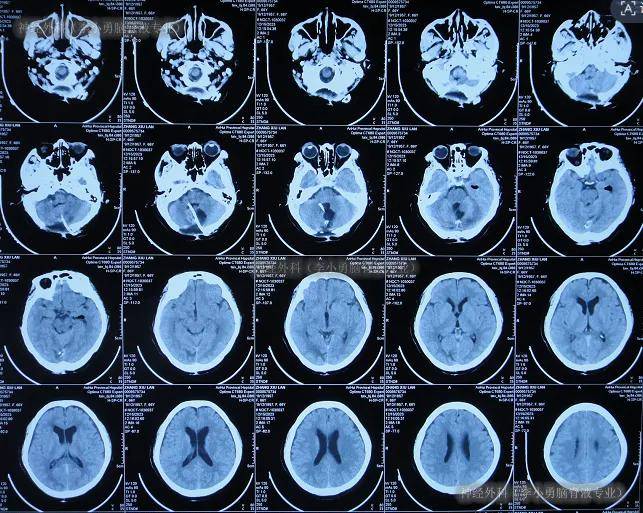

急送至安徽省某三甲医院,查头颅ct示蛛网膜下腔出血

入院时头颅ct示双侧额顶枕叶及颞叶脑损伤,脑室系统扩张,内见点片状

图-6:2024年10月19日头颅ct入院时头颅ct示双侧额顶枕叶及颞叶脑损伤